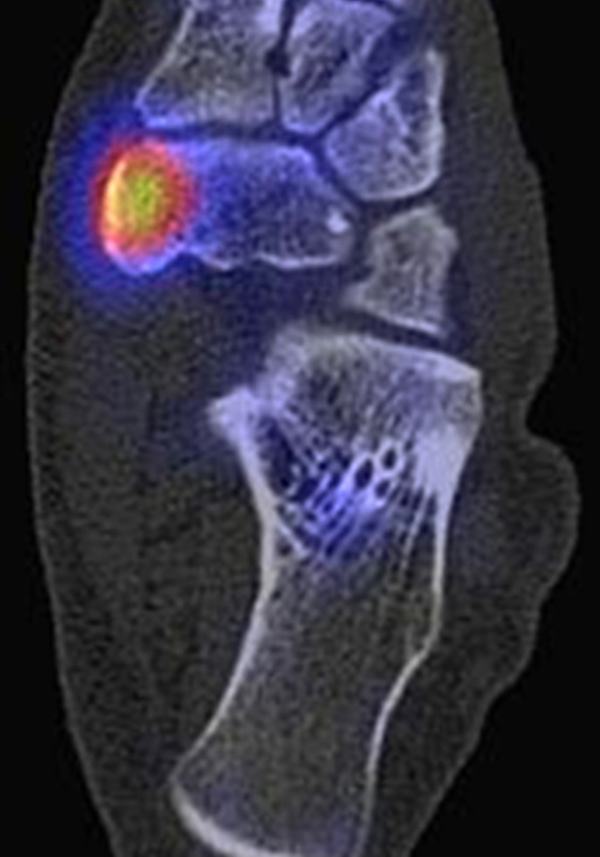

Abbildung 2.1.

Bildbeispiele symptomatische OCL

Zum Lesen der Bildbeschreibung und zur Vollansicht bitte das Bild anklicken. Bild: H. C. Rischke

Abbildung 2.2.

Bilder eines Patienten mit Z. n. mehrfachen Sprunggelenksdistorsionen in der Vergangenheit, besonders heftige Distorsion des linken Sprunggelenkes 5 Wochen vor der Untersuchung. Die SPECT/CT zeigt eine instabile osteochondrale Läsion mit deutlicher Aktivierung.

Abbildung 2.3.

Klärung bei Schmerzen im rechten OSG bei OCL an der medialen Talusschulter. Z. n. OSG-Distorsion vor 2 Jahren und Z. n. OSG-Fraktur / Syndesomosenruptur. Ausgedehnte OCL, hier jedoch kein erhöhter Knochenmetabolismus; lediglich Nachweis einer Stressreaktion im Bereich der Synchondrose eines Os trigonum als Schmerzursache.